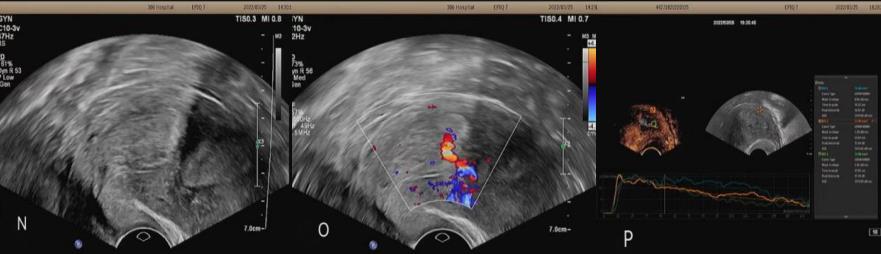

病例4:女,58岁,主因“绝经后6年,子宫内膜增厚5年”入院。常规超声:宫内膜厚度约1.9cm,回声不均匀,可见无回声。超声造影:增强早期,宫腔内病灶区血流灌注晚于子宫肌层,其内可见一分支状血管早于内膜灌注,呈持续性高增强。造影提示:子宫内膜增厚并不均质病变(不支持恶性征象),考虑子宫内膜增生伴息肉。术后病理:萎缩性子宫内膜息肉。